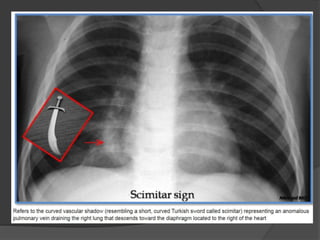

Scimitar syndrome

(also known as pulmonary venolobar syndrome or hypogenetic lung syndrome)

Pathology

It is essentially a combination of pulmonary hypoplasia and partial anomalous pulmonary

venous return (PAPVR). It almost exclusively occurs on the right side.

Haemodynamically, there is an acyanotic left to right shunt.

The anomalous vein usually drains into –

•IVC : most common

•right atrium or portal vein

The lung is frequently perfused by the aorta, but the bronchial tree is still connected and

thus the lung is not sequestered.

Radiographic features

The diagnosis is made by by CT or MR angiography.

Plain film

CXR findings are that of a small lung with ipsilateral mediastinal shift,

The anomalous draining vein may be seen as a tubular structure paralleling the

right heart border in the shape of a Turkish sword (“scimitar”).

Coronal reformat contrast-enhanced CT demonstrates right pulmonary venous drainage

into the inferior vena cava at the level of the diaphragm.